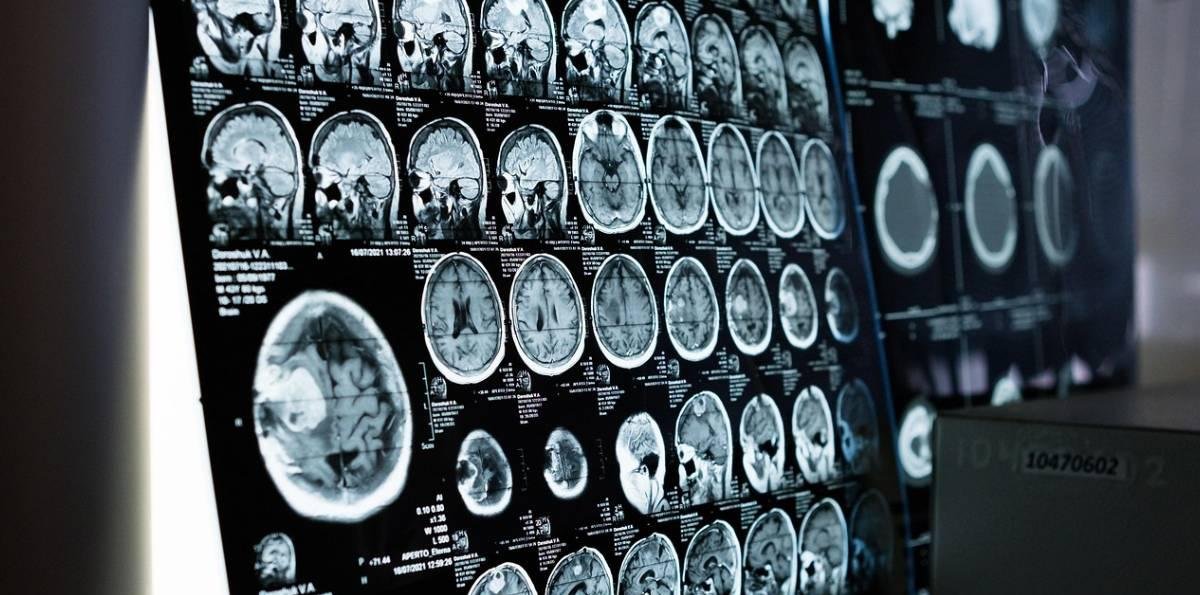

Una investigación encabezada por la Universidad Northwestern (EE.UU) identificó cuándo y dónde se acumulan las proteínas tóxicas en el cerebro de los pacientes con alzhéimer.